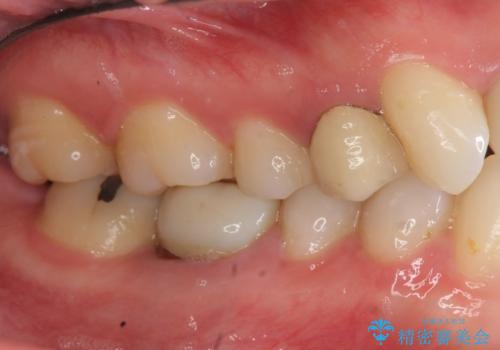

- 治療途中の歯を3年放置した結果、ファイバーコア下に虫歯が再発し抜歯を余儀なくされました。

インプラント治療ではなく手術の必要のないブリッジ治療を希望・選択されたので治療を進めます。

最終的なクラウンを入れずコアのまま、仮歯のまま長期間過ごすと虫歯が再発し残すことが難しくなってしまうことがあります。